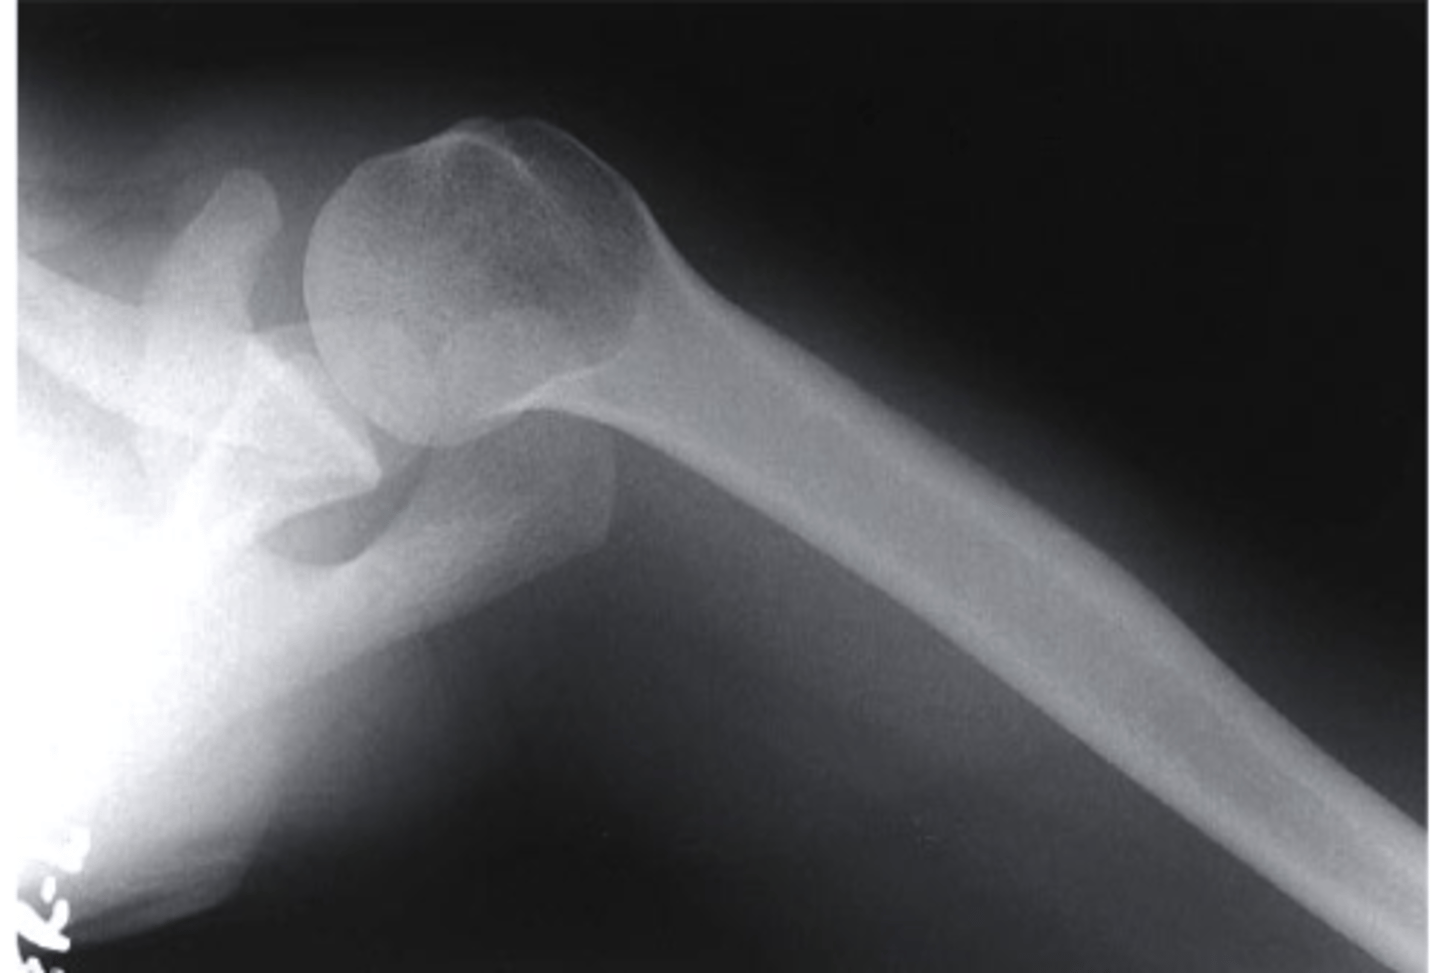

scapular Y lateral

what view is this

clavicle

what does the pink line point to?

coracoid process

acromion of scapula

humeral head

inferior angle of scapula

body of scapula